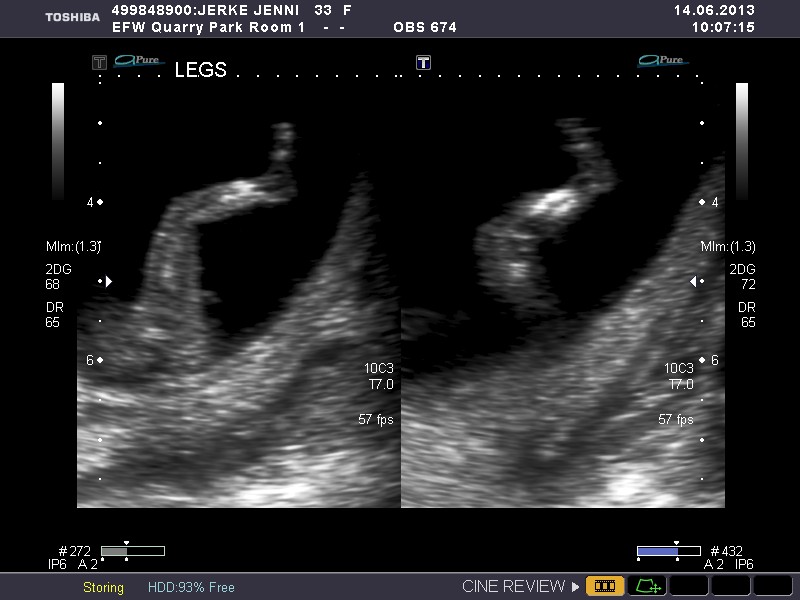

Please give me your best guess as to wether the baby in this ultrasound is a boy or girl.

Leaning girl if ultra sound of potty shot is over 16 weeks xx